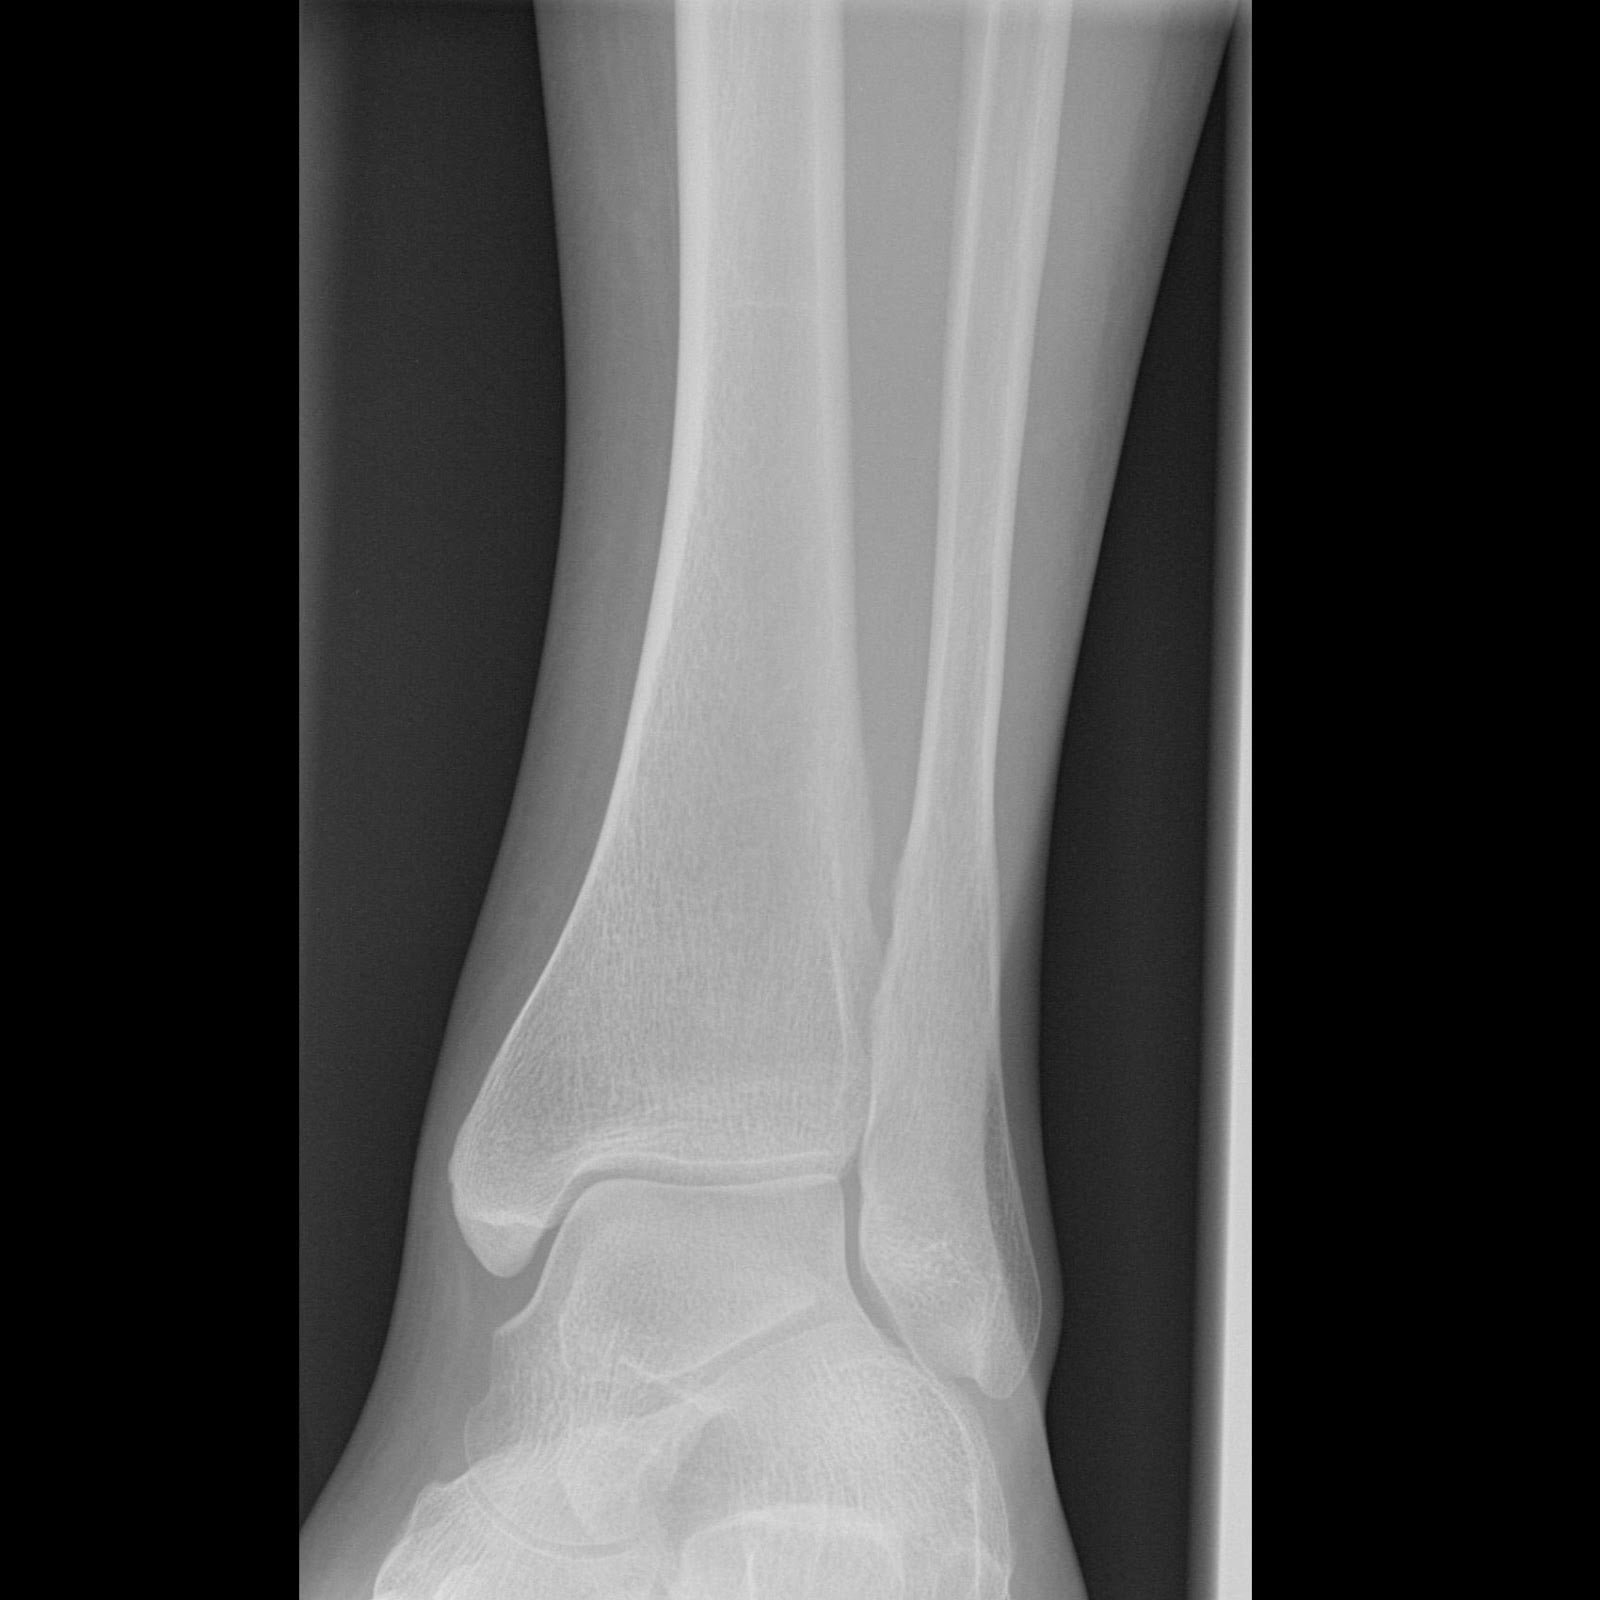

Broken ankle x-rays are crucial diagnostic tools used by medical professionals to assess and treat ankle injuries. These radiographic images provide detailed views of the ankle’s bony structures, allowing doctors to identify fractures, dislocations, and other abnormalities. But what exactly do these x-rays reveal?

X-rays of broken ankles typically show one or more of the following:

- Fractures in the tibia (shinbone)

- Breaks in the fibula (outer lower leg bone)

- Damage to the talus (ankle bone)

- Displacement of bones

- Joint misalignment

Interpreting Broken Ankle X-Rays: What Do Doctors Look For?

When examining broken ankle x-rays, what specific features do medical professionals focus on? Doctors look for several key indicators:

- Fracture lines: Visible breaks or cracks in the bones

- Bone displacement: Misalignment of bone fragments

- Joint space widening: Indicates ligament damage or instability

- Soft tissue swelling: May suggest additional injuries

- Presence of loose bone fragments: Can complicate healing

By carefully analyzing these features, doctors can determine the severity of the fracture, assess joint stability, and develop an appropriate treatment plan tailored to the patient’s specific injury.